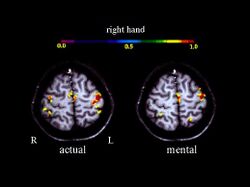

Activation in the motor cortex during motor imagery amounts about 30 % of the level observed during actual performance; Roth et al., 1996.

A large number of functional neuroimaging studies have demonstrated that motor imagery is associated with the specific activation of the neural circuits involved in the early stage of motor control (i.e., motor programming). This circuits includes the supplementary motor area, the primary motor cortex, the inferior parietal cortex, the basal ganglia, and the cerebellum.[21][22] Such physiological data gives strong support about common neural mechanisms of imagery and motor preparation.[23]